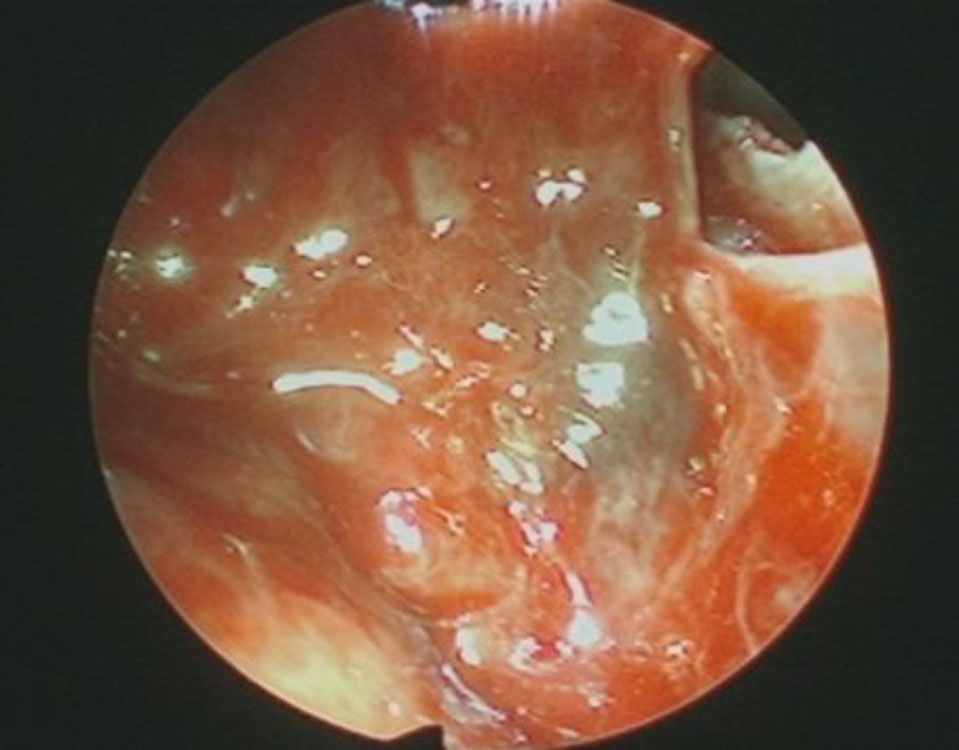

711

'25年12月

60代

良性頭蓋咽頭腫

頭蓋内腫瘍摘出術

No.’25_113 摘出 前

No.’25_113  摘出 中

No.’25_113 摘出 後